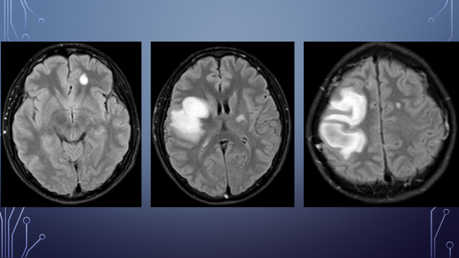

Deterioro neurológico: parálisis de miembro superior izquierdo y hemiparesia izquierda.

Ingresa al HGZ en Cancún, Q. Roo, con traslado a la UMAE Mérida

Interrogatorio indirecto (hermana) por el servicio de RM:

APNP: Abuso sexual a los 9 años, homosexual, IVSA: 14 años, NPS:6, toxicomanías (+): alcohol, tabaco, cocaína y marihuana desde los 15 años, convive con familiar (primo) VIH positivo desde hace un año.